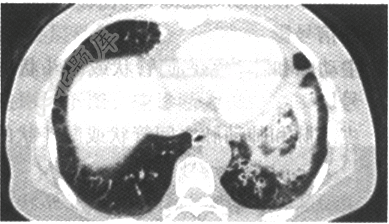

- 单项选择题患者,女,57岁,咳嗽、咳痰2个月余,3天前咯鲜血一次,约5ml。胸部CT扫描如图,则应诊断是

A、支气管扩张

B、肺泡蛋白沉积症

C、周围型肺癌

D、支气管肺炎

E、中央型肺癌